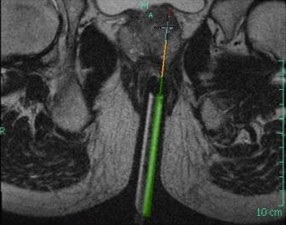

MRI-Guided Prostate Biopsy

Results from PRECISE Trial

Here’s welcome news for men of a certain age: These new results from the PRECISE trial appear to support a less invasive approach to investigations for suspicion of prostate cancer (PCa).

An approach using MRI of the prostate followed by targeted biopsy (TB) in men with images suggesting a high risk had better results than the conventional approach of using transrectal ultrasound systematic biopsy. Results come from the phase 3 PRECISE trial and were published online in JAMA Oncology last month.

The trial showed that, by taking an imaging-first strategy, you could reduce the number of men needing a biopsy by about 40% and actually find more significant cancer. The approach also appeared to reduce the number of indolent tumours and reduce the risk of overtreatment.